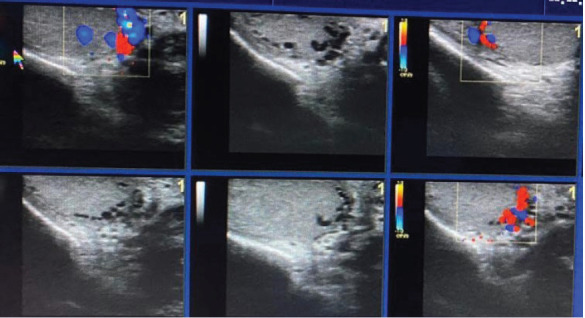

Results: Of the 20 patients with ITV, 2 had isolated ITV, and the remaining had ITV accompanying ETV, of whom only one had a right ETV. One patient had left testicular atrophy accompanying an isolated ITV. Among the ITV cases, subcapsular ITV was the most common (n=13), followed by central ITV (n=4) and subcapsular and hilar ITV (n=3). The patients' ages ranged from 18 to 30 years.

Conclusion: ITV is a rare clinical entity that occurs only in young men, with most cases accompanying ETV. ITV is generally peripherally located in the testicular parenchyma. In this study, no correlations were found between ITV, ETV, and age. As in this study, testicular atrophy is rarely observed in patients with ITV. No studies have presented ITV cases with spermiogram analysis results. Thus, the effect of ITV on male reproductive fertility is still unknown, and further study on this topic is needed.